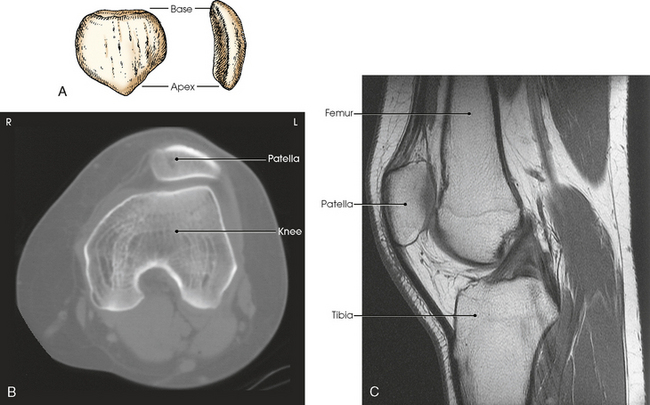

The patella, or knee cap (Fig. 6-8), is the largest and most constant sesamoid bone in the body (see Chapter 3). The patella is a flat, triangular bone situated at the distal anterior surface of the femur. The patella develops in the tendon of the quadriceps femoris muscle between 3 and 5 years of age. The apex, or tip, is directed inferiorly, lies ½ inch (1.3 cm) above the joint space of the knee, and is attached to the tuberosity of the tibia by the patellar ligament. The superior border of the patella is called the base.

Fig. 6-8 A, Anterior and lateral aspects of patella. B, Axial CT scan of patella showing relationship to femur. C, Sagittal MRI showing patellar relationship to femur and knee joint. Apex of patella is ½ inch (1.2 cm) above knee joint. (B and C, Modified from Kelley LL, Petersen CM: Sectional anatomy for imaging professionals, ed 2, St Louis, 2007, Mosby.)